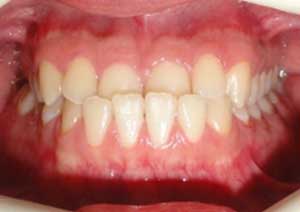

Le cross-bite antérieur (ou articulé croisé antérieur) est une anomalie d’occlusion dans laquelle une ou plusieurs dents du maxillaire se retrouvent en arrière des dents mandibulaires, alors qu’elles devraient être en avant.

Traitement : Dans ce cas, nous avons eu recours à la mise en place de cales postérieures en résine bleue au niveau des premières molaires maxillaires, Elles ont permis de séparer temporairement les mâchoires afin de laisser les dents du haut se replacer correctement devant celles du bas, corrigeant ainsi le cross-bite antérieur.

Avant